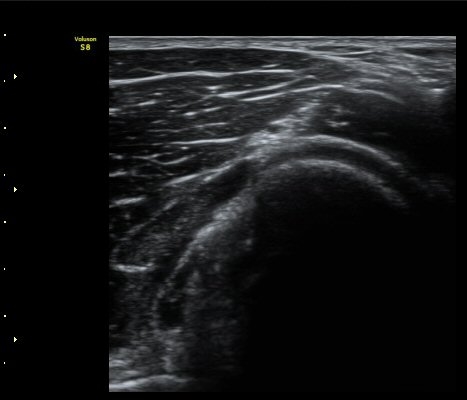

ÃÊÀ½ÆÄ °Ë»ç

¼ÒµÎ Ⱦ´Ü¸é°Ë»ç¿¡¼­ ¿ä°ñ½Å°æ Èİñ°£½Å°æÀÌ Á¤»óÀûÀ¸·Î °í³ªÂûµÈ´Ù(±×¸² 1).

ŽÃËÀÚ¸¦ ¿ä°ñµÎ ºÎÀ§·Î À̵¿ÇÏ´Ï ¿ä°ñµÎ Ç¥Ãþ¿¡ Àú¿¡ÄÚ ³¶Á¾ÀÌ °üÂûµÇ°í ³¶Á¾ÀÇ ¿ÜÃø¿¡¼­

Èİñ°£½Å°æÀÌ ¾Ð¹ÚµÇ°í ÀÖ´Ù(±×¸² 2).

ŽÃËÀÚ¸¦ Á» ´õ ¸»´ÜÀ¸·Î À̵¿ÇÏ´Ï ³¶Á¾Àº ´õ Å©°Ô °üÂûµÈ´Ù(±×¸² 3, 4).

¿ä°ñÀ» Á¾´Ü¸éÀ¸·Î °üÂûÇÏ´Ï ¿ä°ñ ±ÙÀ§ºÎ Ç¥Ãþ¿¡ ³¶Á¾ÀÌ È®Àεǰí(±×¸² 5) ŽÃËÀÚ¸¦

Á¶ÀýÇÏ´Ï Èİñ°ß½Å°æÀÇ Á¾´Ü¸é À̹ÌÁö°¡ °üÂûµÇ´Âµ¥ ³¶Á¾¿¡ ÀÇÇØ Ç¥ÃþÀ¸·Î ÀüÀ§µÇ¾î

ÀÖ´Ù(±×¸² 6,7). ±×¸² 8. ³¶Á¾°ú Èİñ°£½Å°æ ÁÖÀ§¾Ö¼­ °üÂûµÇ´Â µ¿¸Æ.